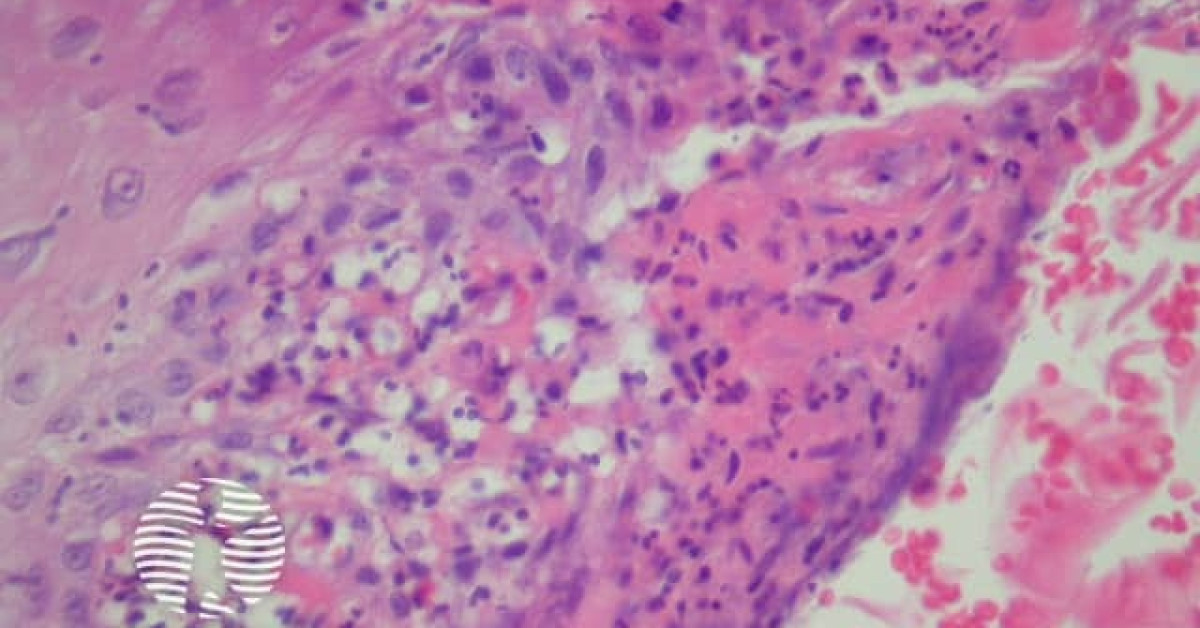

Blastomycosis-like pyoderma is a cutaneous condition characterized by large verrucous plaques with elevated borders and multiple pustules.: 255, 272